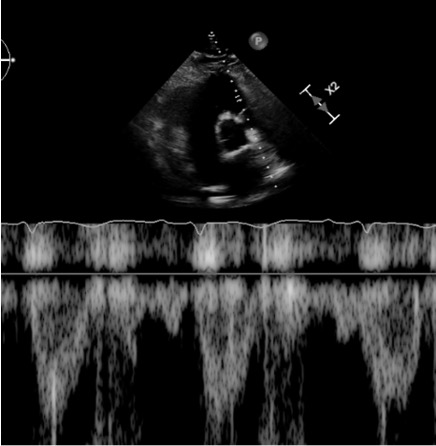

Case Presentation: A 62-year-old man presented to the emergency department with chest pain and dyspnea after recently driving from Michigan to Florida. In the ER, he was hypertensive and tachypneic with normal saturations. EKG showed sinus tachycardia with a classic S1Q3T3 pattern. Labs revealed an elevated D-dimer and troponin. CTA chest revealed a large saddle pulmonary embolism (PE) at the bifurcation of the pulmonary artery trunk into the right and left main pulmonary arteries, filling defects throughout both lungs and signs of right ventricular (RV) strain. Transthoracic echocardiogram (TTE) revealed early systolic notching of the right ventricular outflow tract (RVOT) envelope, dilated right atrium and ventricle, moderate to severely impaired RV function, and a right ventricular systolic pressure (RVSP) of 38 mm Hg (Figure 1). He emergently underwent bilateral suction thrombectomy with a moderate amount of thrombus extracted from the left and right pulmonary arteries. The end of the procedure was complicated by brief pulseless electrical activity requiring CPR with one round of chest compressions before ROSC. A stat TTE revealed a large, serpentine thrombus in transit between the right atrial and ventricle, for which tissue plasminogen activator (tPA) was given. Repeat CTA chest showed improvement in PE and the development of hemopericardium. TTE confirmed the effusion and tamponade physiology. The patient underwent pericardiocentesis for cardiac tamponade with eventual improvement in hypoxia and hemodynamics. Repeat TTE showed the resolution of early systolic notching of the RVOT waveform, mild to moderately impaired right ventricle systolic function, bi-atrial dilation, mild to moderate mitral regurgitation, moderate tricuspid regurgitation, mild pulmonic valve regurgitation, and an increase in RVSP to 42 mm Hg (Figure 2). Hypercoagulopathy workup found a heterozygous Factor V Leiden mutation, and long-term anticoagulation with apixaban was implemented.

Discussion: We present a case of high-risk submassive PE in which systolic notching of the right ventricular outflow tract resolved after thrombectomy and tPA. Echocardiographic findings correlating to RV function, such as RV dilation, right ventricular systolic pressure (RVSP), and tricuspid annular plane systolic excursion (TAPSE), lack specificity for elevated pulmonary vascular resistance (PVR). Notching of the pulse wave doppler envelope at the RVOT is a specific finding for elevated PVR in pulmonary arterial hypertension and is increasingly recognized as a tool in acute pulmonary embolism.1,2,3 Early systolic notching of the RVOT waveform may be more specific in acute PE than other more cited findings, such as the 60/60 sign.1 This finding may indicate that the resolution of RVOT notching is a useful tool for assessing response and risk after treatment of acute pulmonary embolism. There is a lack of literature describing the utility of monitoring the resolution of RVOT notching when assessing response to interventions in RV failure.

Conclusions: This case highlights the value of the shape of the RVOT envelope when diagnosing and assessing response to treatment in acute PE. Failure to resolve RVOT notching may prove to be an indication of inadequate response to treatment, and further studies are warranted. This case also highlights RVSP’s limitations and lack of specificity since the patient’s RVSP increased after hemodynamic improvement.